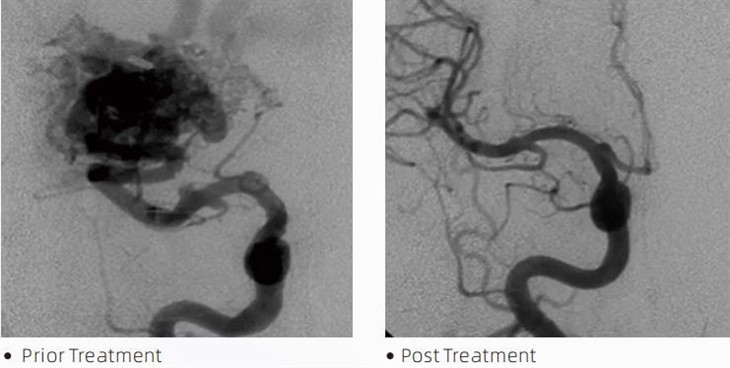

LavaTMLa colla embolica è un dispositivo medico utilizzato dai neuroradiologi interventisti durante le procedure minimamente invasive per trattare condizioni come aneurismi cerebrali, malformazioni artero-venose e tumori. La colla embolica Lava offre molteplici vantaggi sia ai professionisti medici che ai pazienti in termini di sicurezza, facilità d'uso ed efficacia. La lava è in grado di sigillare i vasi sanguigni in modo rapido ed efficiente. Il processo prevede l'iniezione della colla direttamente nel vaso mirato, dove polimerizza e si indurisce in una massa simile a un calco che riempie l'aneurisma o la malformazione. Quindi interrompe efficacemente il flusso sanguigno alla lesione, prevenendone la rottura e riducendo il rischio di danni permanenti o ictus. Lava include Lava-12, Lava-18 e Lava-34. Ciascuna formulazione è studiata per soddisfare esigenze cliniche specifiche. Lava-18 è una formulazione standard per uso generale. Lava-34 è una colla ad alta viscosità per recipienti ad alto flusso. Mentre Lava-12 ha una viscosità inferiore ed è più fluido, consentendo microvasi distali. Con queste opzioni, i neuroradiologi interventisti possono scegliere le formulazioni Lava adatte per garantire risultati ottimali. Una delle caratteristiche più notevoli di Lava è la sua proprietà non adesiva. Questa sostanza è appositamente formulata per rimanere stabile fino a quando non raggiunge l'area mirata. Questa caratteristica significa che la colla embolica Lava può essere posizionata con precisione all'interno dell'arteria e rimanere lì senza attaccarsi o legarsi al tessuto circostante.